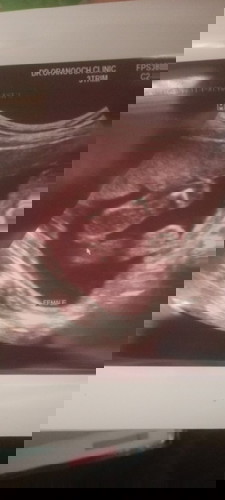

หญิงหรือชายคะ

หมอบอกอาจหญิงเพราะเห็นไม่ชัด

น่าจะ ญ นะคะ🥰